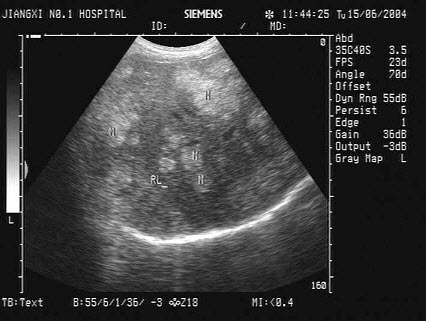

某患者右肾区疼痛数日,体温38℃。根据该患者右肾声像图表现,最可能的超声诊断为()

A.肾周围炎

B.肾炎

C.肾结石

D.肾结核

E.肾周血肿